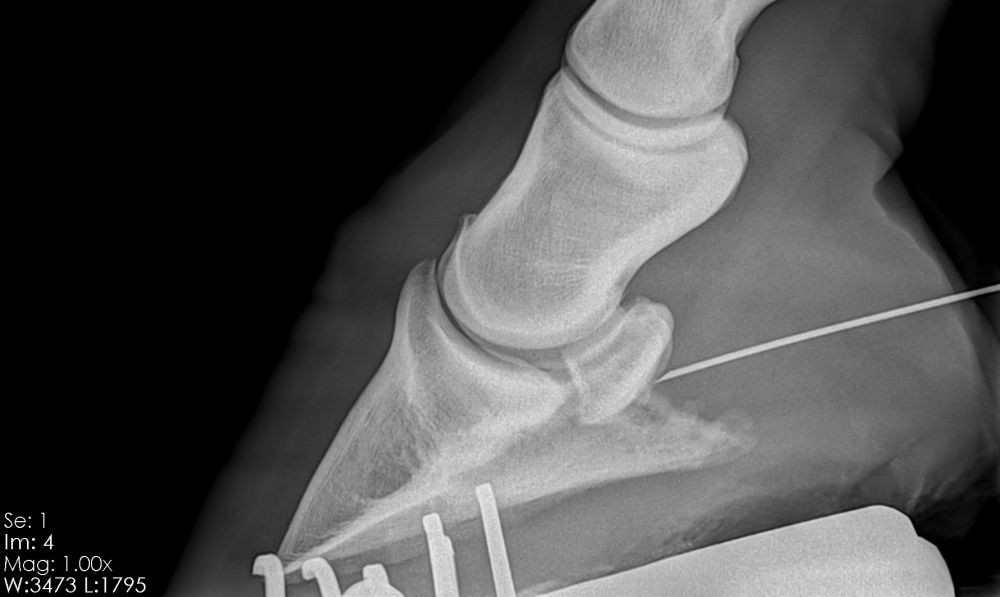

At Dorset Equine we have the best portable digital DR x-ray system available.  It allows us to take high quality x-rays which appear as digital images on the screen within 3 seconds, meaning radiography time is kept to a minimum and an immediate diagnosis can be given.

Our x-ray system is fully mobile so can be used with ease at your yard or at our Whitcombe clinic.

If required, our digital system allows us to instantly send images to your farrier via email which proves invaluable in assisting with corrective farriery.  When a referral to an orthopaedic specialist is required it also enables us to send the across the relevant images prior to the horses arrival at their practice.